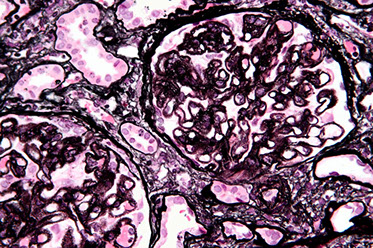

LM: large, hypercellular glomeruli c endothelial and mesangial cellular prolif; accentuated lobular appearance and mesangial (cell) interposition bwt endothelium and GBM c IC deposits in same region causing double contouring of capillary wall BM on silver stain

IF: prominent granular C3, c IgG, sometimes C1q (in capillary walls and mesangium)

Type I EM: "tram-track" appearance 2/2 GBM splitting caused by new BM material bwt original GBM and endothelial cells